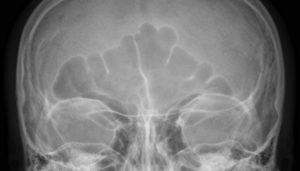

На втором этапе делается фронтальный снимок головы пациента, для чего его располагают лицом вниз таким образом, чтобы сосцевидные отростки совпадали.

На фронтальном снимке врачу можно будет рассмотреть:

- венечный шов;

- чешую лобной кости;

- передние участки теменных костей.